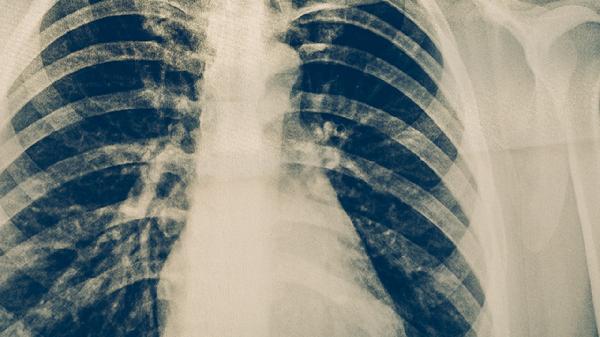

肺结核患者的饮食事项

肺结核患者需注意高蛋白、高热量、高维生素饮食,避免辛辣刺激及酒精。肺结核是由结核分枝杆菌引起的慢性传染病,合理饮食有助于增强免疫力、促进病灶修复。主要饮食原则包括适量增加优质蛋白摄入、补充维生素A/C/D、保证充足热量,同时限制可能加重咳嗽或影响药物吸收的食物。